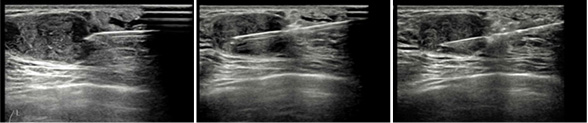

초음파검사는 물체에 닿아 되돌아오는 음파를 이용해 유방 내의 영상을 얻으며, 낭종과 종양의 감별, 종양의 크기, 모양, 밀도 등을 결정하여 유방암과 양성 종양을 감별할 수 있게 합니다. 또한 초음파는 병변을 진단하고, 암이 의심되는 병변을 초음파 유도 하에 조직생검을 가능하게 하여 수술에 의한 조직생검을 거의 대치할 수 있습니다.

- 초음파를 이용하며 맘모톰을 비롯, 각종 조직검사를 할 수 있습니다.

유방조직검사

저희 병원에서는 환자의 안전을 위해 모든 진단 및 치료용 특수 바늘(조직검사 및 맘모톰)의 일회 사용 원칙으로 하고 있습니다.